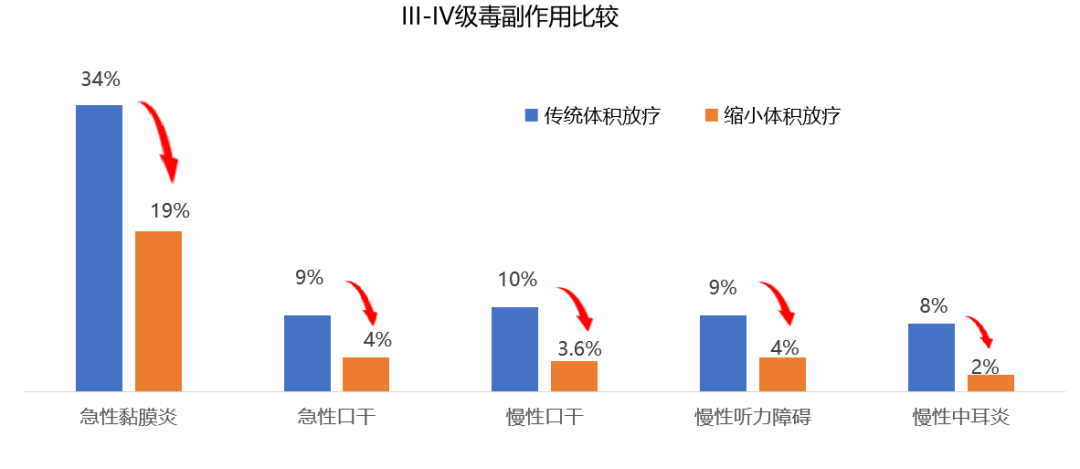

对于鼻咽癌的治疗,放射治疗是主要治疗手段。国际指南推荐,局部晚期鼻咽癌以“化疗+同期放化疗”的综合治疗。化疗使90%患者肿瘤显著缩小,而既往国际专家共识推荐放疗照射范围仍需包括化疗前肿瘤大小。这导致放疗时周围正常组织(如内耳、腮腺)接受高剂量辐射,引发口干、听力损伤等不可逆副作用,放疗相关毒性发生率高,严重影响患者生活质量。

与传统放疗组相比,化疗后治疗范围放疗并没有增加复发,却显著降低了毒副反应,同时,患者整体健康状态、体力状态、情绪功能显著改善,口干及唾液黏稠症状明显减轻。

因此,这项多中心III期临床试验证实,仅照射化疗后的肿瘤范围,并没有增加复发,却显著降低了毒副反应,显著改善患者生活质量,使我国鼻咽癌诊疗实现从"保生存"到"优生存"的跨越式突破!